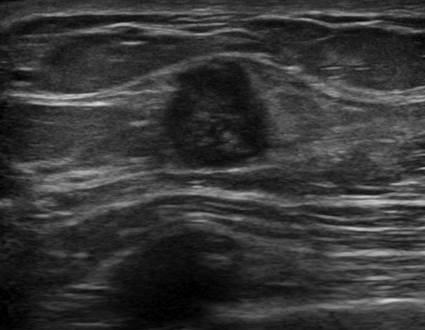

Ung thư tuyến vú

» Thông tin: Nữ giới – 45 tuổi.

» Lâm sàng: Kiểm tra sức khỏe.